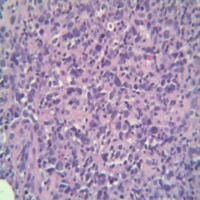

Category: Lymphoma: Mature B-cell and Plasma cell Neoplasms > Large B-cell lymphomas (not Richter transformation)